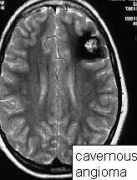

问:什么是 脑海绵状血管瘤 ? 答:脑海绵状血管瘤也称为海绵状血管畸形。这些名称是指人们通常在大脑或脑干中有一群聚集的血管畸形,这种血管畸形会扩大或扩张,并且随着时间...

问:脑海绵状血管瘤是什么原因造成的? 答: 脑海绵状血管瘤是脑和脊髓中小血管(毛细血管)的异常集合,其结构扩大且不规则。这些毛细管具有异常薄的壁,并且它们缺少其他支...